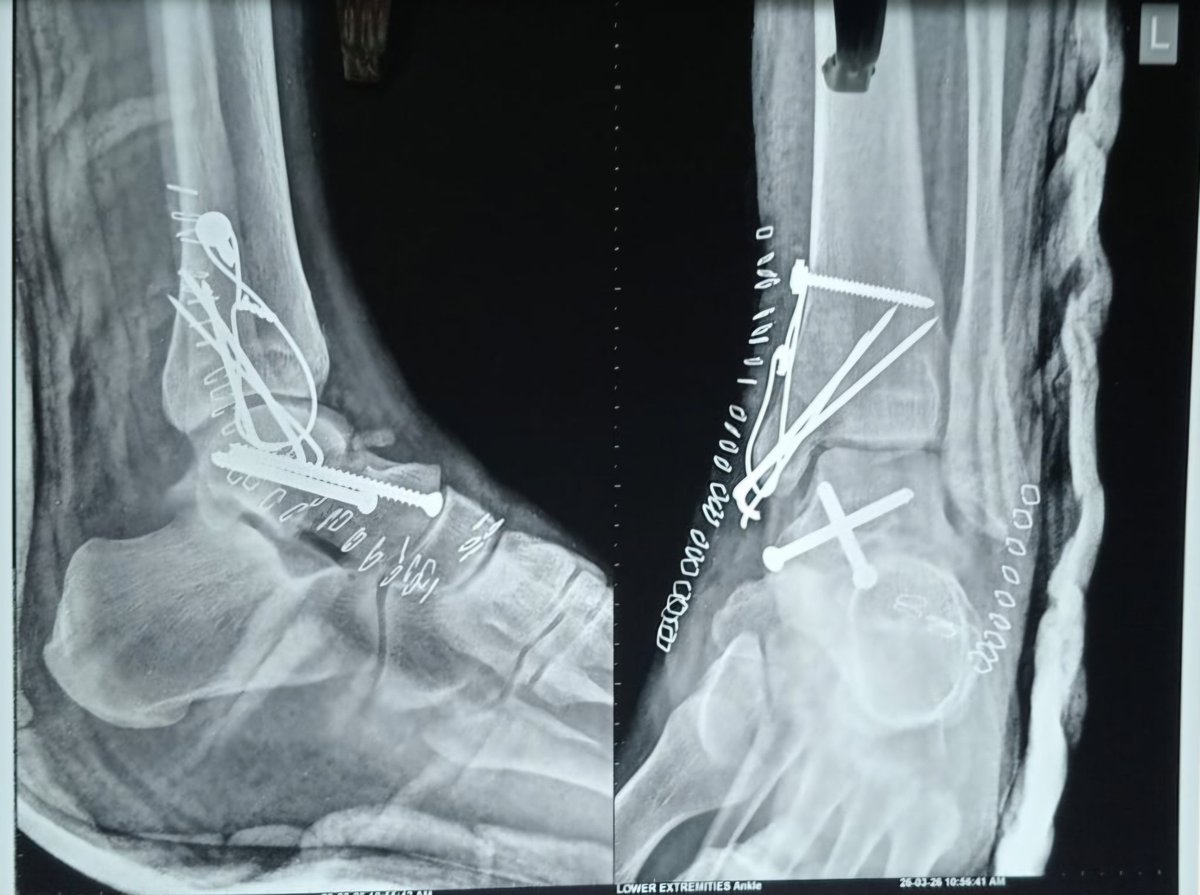

@Drlyndonmason Comminuted pieces used to fill defect as BG Lateral fully threaded position screw Medially partial threaded cancellous screw Your views regarding outcome with / without plate ?

#orthotwittter @Drlyndonmason # talus Closed injury Body dislocated & locked PM side MM # Lateral comminution Not on medial side Dual approach Joint distraction using double bend Hintermann Pins in distal tibia & navicular keeping Foot in plantar flexed Valuable feedback🙏🙋